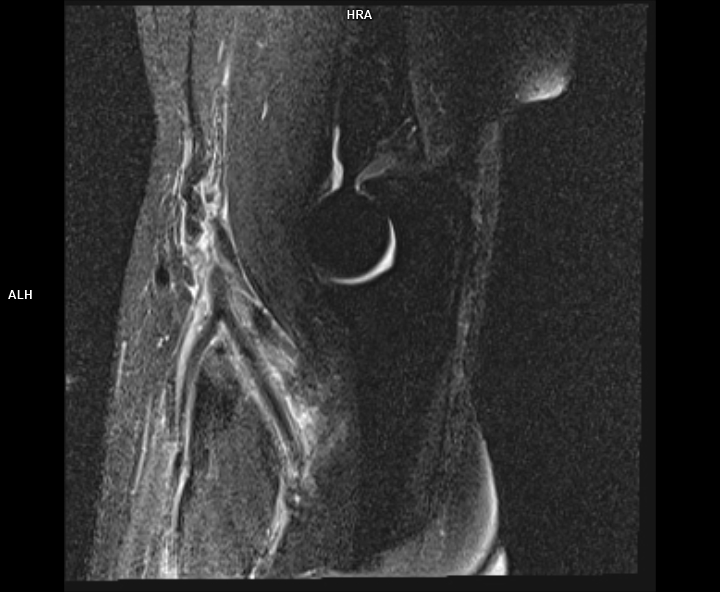

Figura 2: achiziție sagital T2 cu saturația grăsimii la nivelul cotului cu evidențierea tendonului de inserție inferioară a mușchiului biceps brahial ce este retractat superior